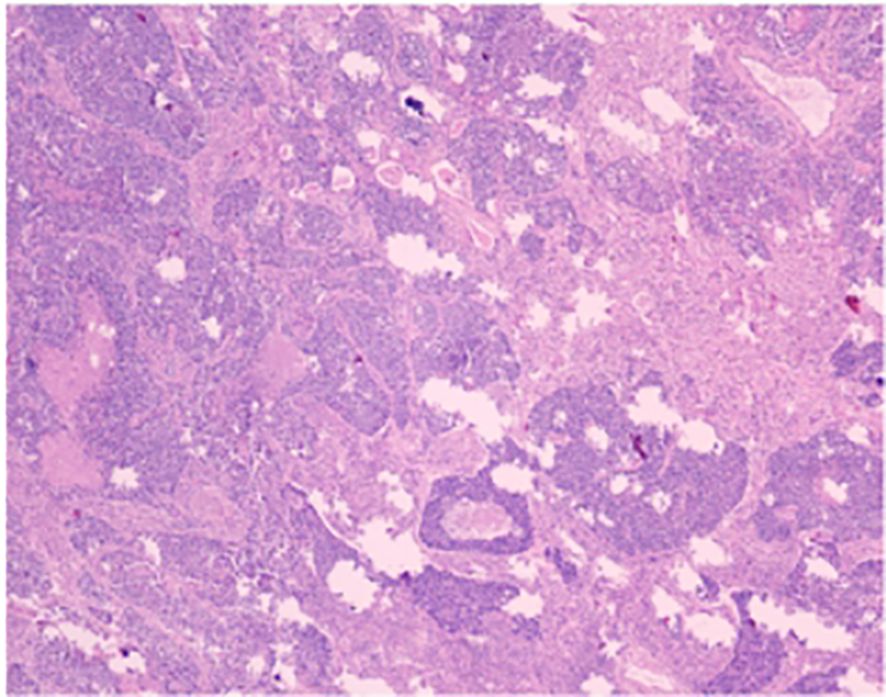

Figure 4

Microscopic view of tissue showing a complex structure with various shades of purple and pink. The image includes irregularly shaped areas of denser and lighter coloration, indicating different tissue types or components.

Figure 4. The conventional paraffin pathology of the left upper lobe nodule indicates the coexistence of small cell lung cancer (SCLC) and large cell lung cancer (LC).

The patient is a 58-year-old male who was admitted to our hospital’s thoracic surgery department on July 26, 2024, due to a “6-month history of a left lung upper lobe nodule discovered during a routine examination.” Approximately 6 months ago, during a routine physical examination at another hospital, the patient underwent a chest CT scan which revealed multiple lung nodules, the largest of which was located in left upper lobe. He subsequently underwent regular follow-up scans. A chest CT scan performed at our hospital showed a lobulated small nodule in left upper lobe, measuring approximately 2.1 cm × 1.6 cm. Multiple small nodules in both lungs, with the largest measuring approximately 0.5 cm, recommended for follow-up examination. No significant enlargement of lymph nodes in mediastinum was observed (Figure 3). The patient reported no symptoms. He has a 10-year history of hypertension and a 30-year history of heavy smoking and drinking. There were no significant findings during physical examination upon admission. Blood gas analysis showed: pH 7.48, blood glucose 10.70 mmol/L, K+ 2.80 mmol/L. Routine blood, urine, and stool tests, liver and kidney function, and coagulation profile were normal. Pulmonary function testing showed FEV1 of 2.76L, indicating mild obstructive ventilatory dysfunction. The electrocardiogram showed no abnormalities. Coronary CTA revealed moderate stenosis in the proximal left anterior descending artery, mild stenosis in the proximal left circumflex artery, and mild stenosis in the right coronary artery in the mid-segment, with no significant narrowing of the other coronary arteries. Brain MRI showed signs of cerebral arteriosclerosis. Ultrasound examinations of the liver, gallbladder, pancreas, spleen, kidneys, adrenal glands, bilateral carotid arteries, bilateral lower extremity veins, and full-body bone scans were all unremarkable. The patient’s family requested surgical treatment for left upper lobe nodule regardless of whether it is benign or malignant. And refused to undergo further relevant tests to clarify the diagnosis. After excluding surgical contraindications, on July 30, the patient underwent a left upper lobectomy under general anesthesia with thoracoscopic surgery. Routine dissection of lymph nodes from groups 5, 6, 7, 9, 10 and 11. Rapid intraoperative frozen section pathology indicated invasive carcinoma and subsequent routine paraffin pathology (Figure 4) showed immunohistochemistry: CK5/6 (-), CK7 (partial +), Napsin A (-), P40 (-), P63 (-), TTF-1 (partial +), CD56 (partial +), CgA (-), Syn (partial +), SSTR2 (-), SMARCA4 (+), CK (+), Ki67 (+, approximately 80%). Based on the immunohistochemistry results, the diagnosis was consistent with a composite small cell carcinoma (neuroendocrine carcinoma + large cell carcinoma). The tumor measured approximately 2.5 × 2 × 2 cm and did not invade pleura. Metastatic cancer was found in the 6th group lymph nodes (2/2) and the 11th group lymph nodes (1/7), no metastatic cancer was observed in other lymph node groups. Based on pathology report, the clinical stage was T1cN2bM0, which corresponds to stage IIIA. Postoperatively, no special treatment was given. After discharge, the patient reported no significant discomfort. Chest CT re-examination at 1st and 10th month post-surgery showed no significant abnormalities (Table 1).